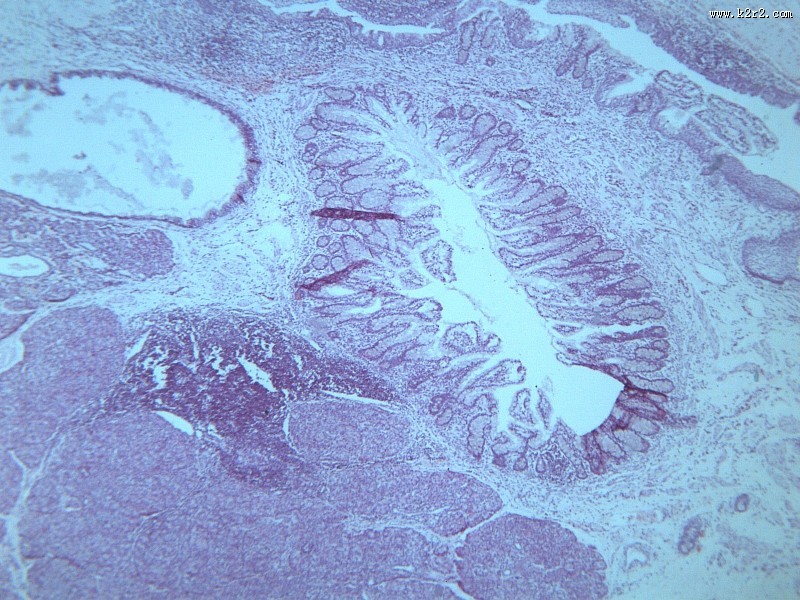

首页 > 其他类别 > 畸胎瘤(12张) > 畸胎瘤 第12张

畸胎瘤 - 第12张